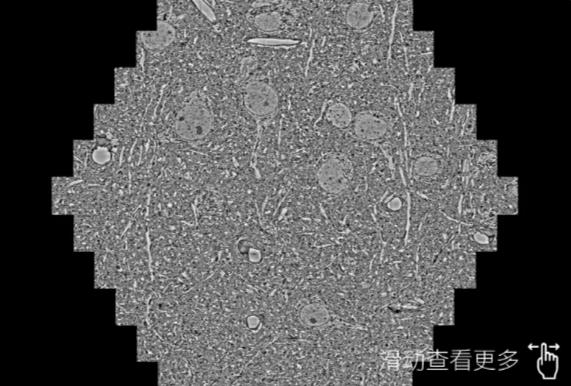

鼠脑切片。左图使用甘南蔡司甘南扫描电镜MultiSEM706对165μmx143pm面积区域成像,耗时仅需1.5秒。右图为鼠脑切片中30μm区域放大效果。样品由芝加哥大学B.Kasthuri提供。